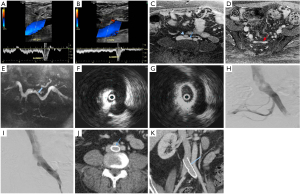

Unilateral swelling of the lower limb is commonly interrogated by physical examination aided by a venous duplex ultrasound of the affected limb. While color Doppler ultrasound is adequate and sensitive for the diagnosis of deep vein thrombosis and evaluation of varicose veins and venous incompetence, it is woefully inadequate to study the pelvic veins, especially the ilio-caval region. If the ultrasound is able to visualize the proximal CIV, it may demonstrate the lack or reduction of phasic variations of blood flow distal to the stenosis and turbulence (color mosaic) at the site of stenosis (Figure 1). The opposite side serves as a control. Venous collaterals, an important component of the diagnostic findings are poorly identified by ultrasound.

MR venography, though uncommonly done for diagnosing MTS, is as accurate as CT in diagnosing the vascular compression, deep vein thrombosis and pelvic venous collaterals. In addition to the post contrast MR venography study (Figure 1), a time-of-flight (TOF) sequence (Figure 1) may identify flow reversal in the internal iliac vein (as such, no signal on 2D TOF) ipsilateral to common iliac vein compression and enlarged ascending lumbar vein in case of a tight iliac stenosis (19). Newer techniques like 4D flow MR venography may provide interesting insights into the flow dynamics like velocity and direction with superior temporal resolution in these patients; however there is lack of comprehensive evidence (20,21). One disadvantage of extracellular MR contrast agents is that they behave like iodinated contrast media with limited time window for imaging and need for repeat contrast administration if the initial imaging is suboptimal. This apparent glitch can be overcome by using blood-pool contrast agents (BPCA) which can remain in circulation for prolonged periods and thus allow a reliable and repeatable examination (22). Gadofosveset trisodium (Ablavar®, Lantheus Medical Imaging, North Billerica, MA) is the most commonly used BPCA for venous imaging. Another agent that has been used as a blood-pool contrast off-label is Ferumoxytol, a superparamagnetic intravenous iron supplement, FDA approved for patients with anemia of renal failure. The contrast effect is due to the strong shortening of T1 and T2* by the iron supplement. Circulation times are longer owing to its larger size and carbohydrate coating, making it suitable as a blood pool agent.

In the past decade, intra-vascular ultrasound (IVUS) has steadily found increasing use in the diagnosis and management of MTS. During the interventional procedure, IVUS can help in documenting and localizing the cause of iliac venous obstruction—spurs and intimal lesions from chronic adherent thrombus. It can also show the dynamic compression by the overlying artery (Figure 1). In addition to helping in re-canalizing the chronic occlusion, it can assess response of MT lesion to angioplasty and stent placement (Figure 1) and presence of residual thrombus thus aiding in continuation of lysis.

Catheter venography has traditionally been considered the gold standard for diagnosis of MTS. However due to its invasive nature, it is nowadays reserved for cases in which endovascular intervention is planned or diagnosis by non-invasive modalities is equivocal. Venography can demonstrate acute thrombosis within the iliac vein or the ilio-femoral veins. Chronic cases are associated with stenosis or occlusion of LCIV with pelvic and retroperitoneal collaterals (Figure 1) and flow reversal in ipsilateral internal iliac vein. Hemodynamic pressure gradient measurement is a valuable adjunct in confirming presence of significant stenotic lesion associated with MTS. May and Thurner (6) advocated measurement of pressure difference between the iliac veins (2 mmHg at rest, 3 mmHg during exercise), whereas Ferris et al. (26) advocated any gradient between the IVC and left iliac vein for diagnosis of hemodynamically significant obstruction.

Patients with isolated iliac vein thrombosis (minority) can have an ipsilateral common femoral venous access for the procedure. More commonly though, the femoral and popliteal veins are simultaneously involved along with the iliac vein, requiring a popliteal venous access. The choice of sheath size depends on the technique of recanalization. Various catheters (e.g., Indigo, Penumbra, USA) and lytic agents (Alteplase or Urokinase) can be used based on operator preference. During catheter directed thrombolysis, the sheath is flushed with heparin as a continuous infusion. Once there is near total or reasonable recanalization, the underlying stenosis at the iliac venous segment can be unmasked (Figure 2). Caution should be exercised in grading venous stenosis during venography as the iliac vein is compressed or flattened anteroposteriorly leading to a “pancake” effect on the angiographic image in the frontal projection (29). Various oblique projections may be needed for accurate estimation of stenosis. Intravascular ultrasound (IVUS) can help in locating and grading the stenosis. An appropriately long balloon of 8 mm or 10 mm diameter is used to perform an initial angioplasty (Figure 2). The results of angioplasty alone are traditionally below par when compared with stenting, irrespective of the post angioplasty result (30). At this point, an IVUS can help assess the response to plain balloon angioplasty and confirm the landing zones for the stent if required. Self-expanding, Stainless steel stents (Wallstent, Boston Scientific, USA) are preferred, because of their higher radial force, long length and flexibility (Figure 2). However, these stents come with niggles of their own; difficulty in precise placement and possibility of foreshortening being a few. As a principle, balloon mounted stents should be avoided as they can be deformed by the arterial pulsation. Multiple stents should also be avoided as they increase the incidence of in-stent stenosis (31). The primary patency rates at 1 year and 5 years were 93.2% and 74.5% respectively and the secondary patency rates at 1- and 5-year at 100% and 92% respectively in one single center experience (31). The 6-year primary patency rate of iliac venous stents is close to 79%, which exemplifies the role of stenting in this setting (32). The distal (downstream) landing zone is still a debatable topic (33). The Wallstent, being a braided stent, is weakest at its ends and this makes the stent vulnerable to being crushed by the culprit RCIA. Hence the interventionists overcome this by landing it in the lowermost vena cava apposing the right lateral wall. But the problem with this technique is it induces a pseudo-intima formation over the caged right common iliac vein surface of the stent resulting in increased incidence of venous thrombosis on the covered side. Newer dedicated laser-cut nitinol venous stents such as the VICI (Boston Scientific) (Figure 1) (34) and VENOVO (Bard) (35) stents have high patency rates and excellent precision at the time of deployment. These stents have higher resistive radial strength preventing the collapse or crushing of the stent by the right common iliac artery and hence can be deployed flush with the ostium of the LCIV. Following the procedure, patients are switched to oral anticoagulation for a period of 6 months and low dose aspirin thereafter. The choice of oral anticoagulation post endovenous therapy is not adequately evaluated in literature. A systematic review of the studies examining endovenous therapy for MTS, revealed that warfarin has been the most commonly used anticoagulant (36). The newer oral anticoagulants, apart from being equally efficacious, certainly have benefits over warfarin including reduced bleeding complications and avoidance of periodic monitoring. Periodic follow up with ultrasound or CT venography at 1, 3, 6 and 12 months and thereafter yearly for stent patency and symptomatic recurrence is important for early diagnosis of stent occlusion and retreatment. Treatment failures are very rare unless there is residual stenosis anywhere in the dilated/stented segment, incomplete clot clearance, suboptimal inflow from femoropopliteal veins or noncompliance to optimal anticoagulation. An immediate treatment failure in the form of acute stent re-thrombosis is addressed with a relook endovenous therapy with correction of the causative factor. Delayed presentation with stent occlusion is approached according to the clinical findings. If the symptoms are subacute or chronic, of mild severity, usually after cessation of anticoagulation, with well collateralized stent occlusion, then a conservative strategy with reinitiation of lifelong anticoagulation is advised. Alternatively, if there is acute onset severely symptomatic venous thrombosis, a repeat endovenous intervention is preferred.